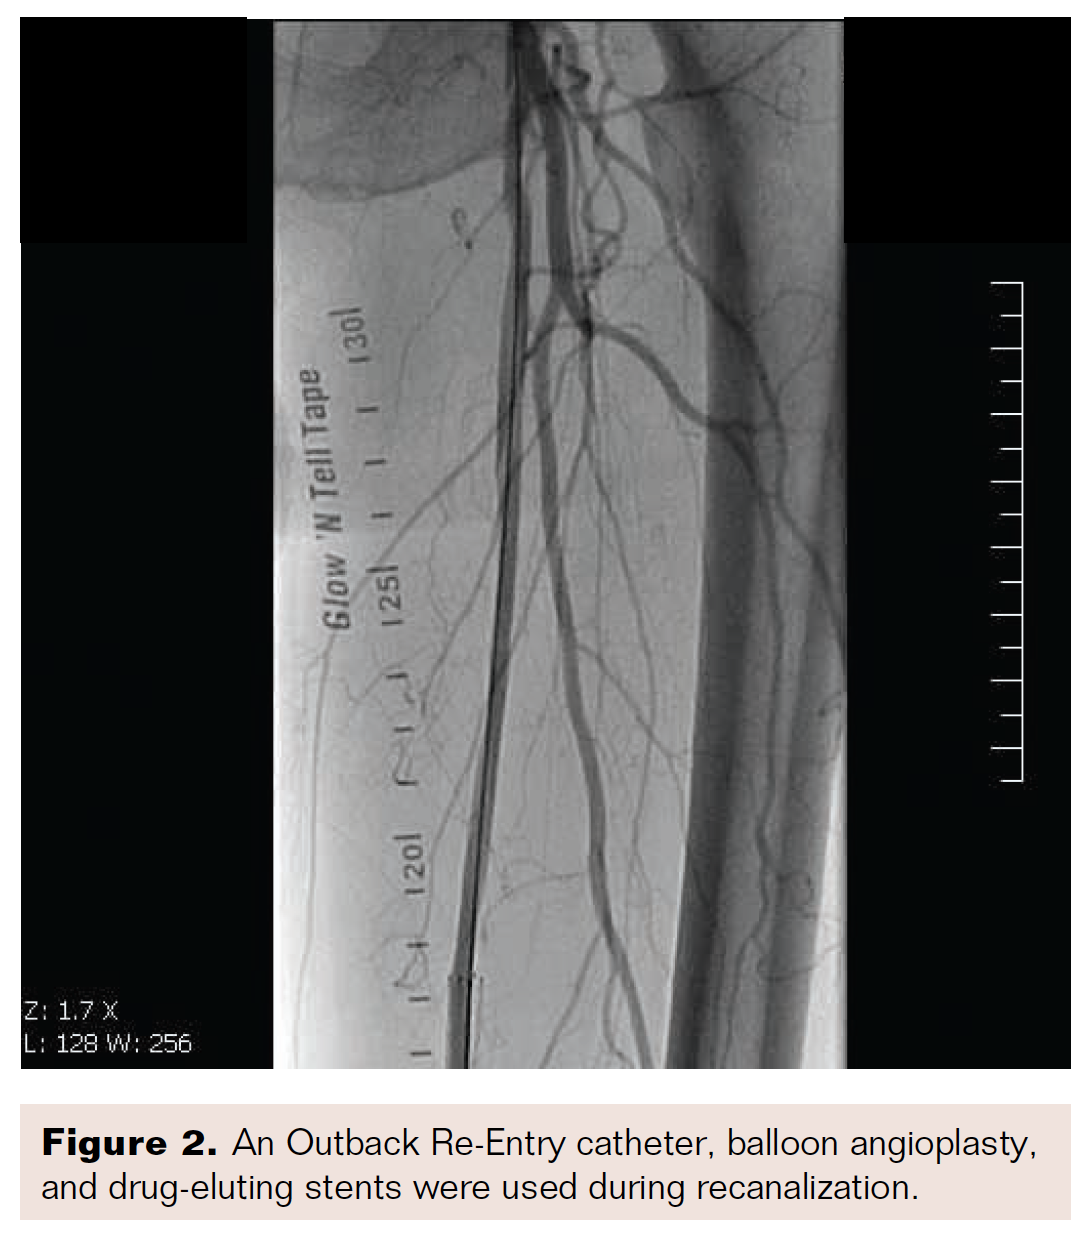

The patient was scheduled for urgent invasive angiography and revascularization, as appropriate. An occluded right SFA (Figure 1) was recanalized using a subintimal approach, which included the use of an Outback Re-Entry catheter (Cordis, a Cardinal Health Company), balloon angioplasty, and placement of drug-eluting stents (Figure 2). Completion angiography showed a satisfactory result throughout the length of right SFA. However, sluggish flow was noted in all three below-the-knee vessels (Video 1: See https://www.vasculardiseasemanagement.com/content/video-supplement-no-reflow-phenomenon-below-knee-vessels-after-percutaneous). Given the involvement of all three vessels and the appearance of the angiography, this sluggish flow was felt to be a slow-flow phenomenon rather than thrombo-embolism. A wire was reintroduced. Intra-arterial nitroglycerin and high doses of adenosine were administered via a microcatheter placed at the level of the popliteal artery, and imaging revealed a significantly improved appearance (Video 2: See https://www.vasculardiseasemanagement.com/content/video-supplement-no-reflow-phenomenon-below-knee-vessels-after-percutaneous).